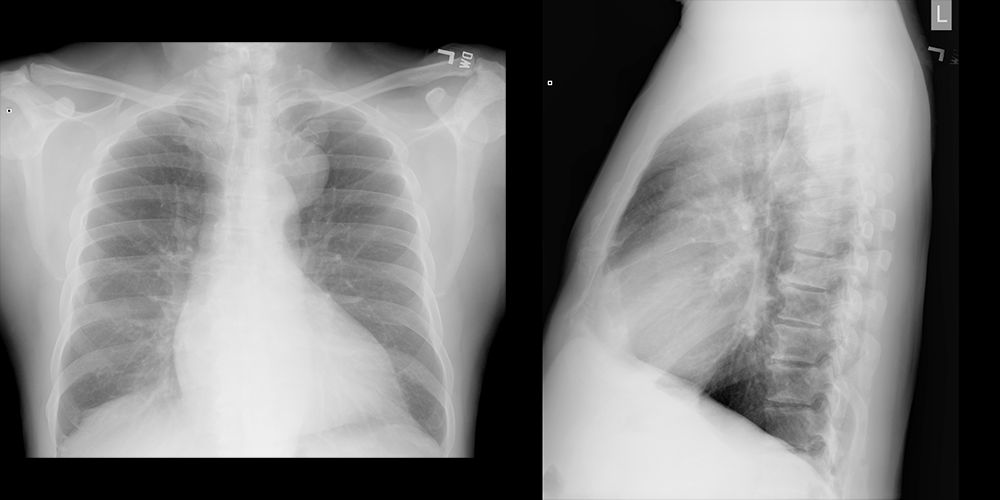

Chest X-ray

What best describes the findings on the Chest X-ray?

There is a well-circumscribed incidental mass in the upper, posterior mediastinum.

View the full study if you'd like to take a look yourself.

Lessons Learned: A posterior mediastinal mass is likely to be a neurogenic tumor. Schwannoma imaging features include a well-circumscribed, heterogeneously enhancing mass.